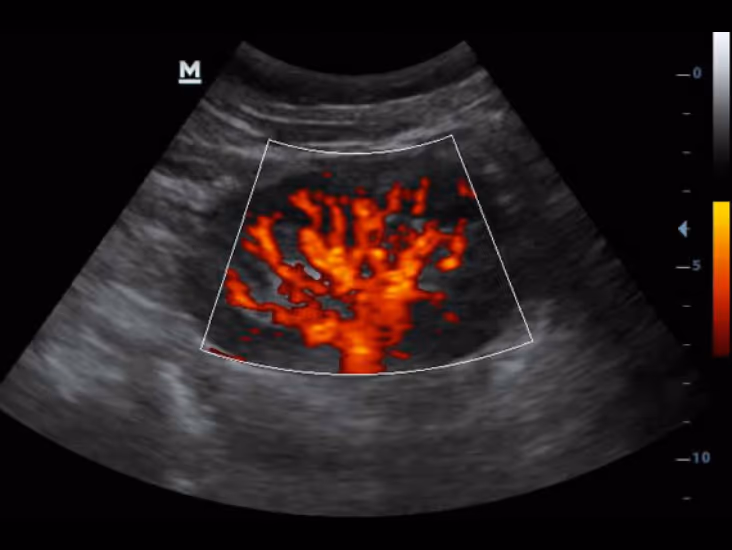

“Power Doppler ve Pulse Wave yazılımları vasküler yapıları tanımlar ve akımların hız grafiklerini elde ederek Dp50 Vet’i siyah beyaz ultrason sisteminin ötesine taşır!”

Power Doppler, Böbrek, Köpek

Power Doppler & Pulse Wave